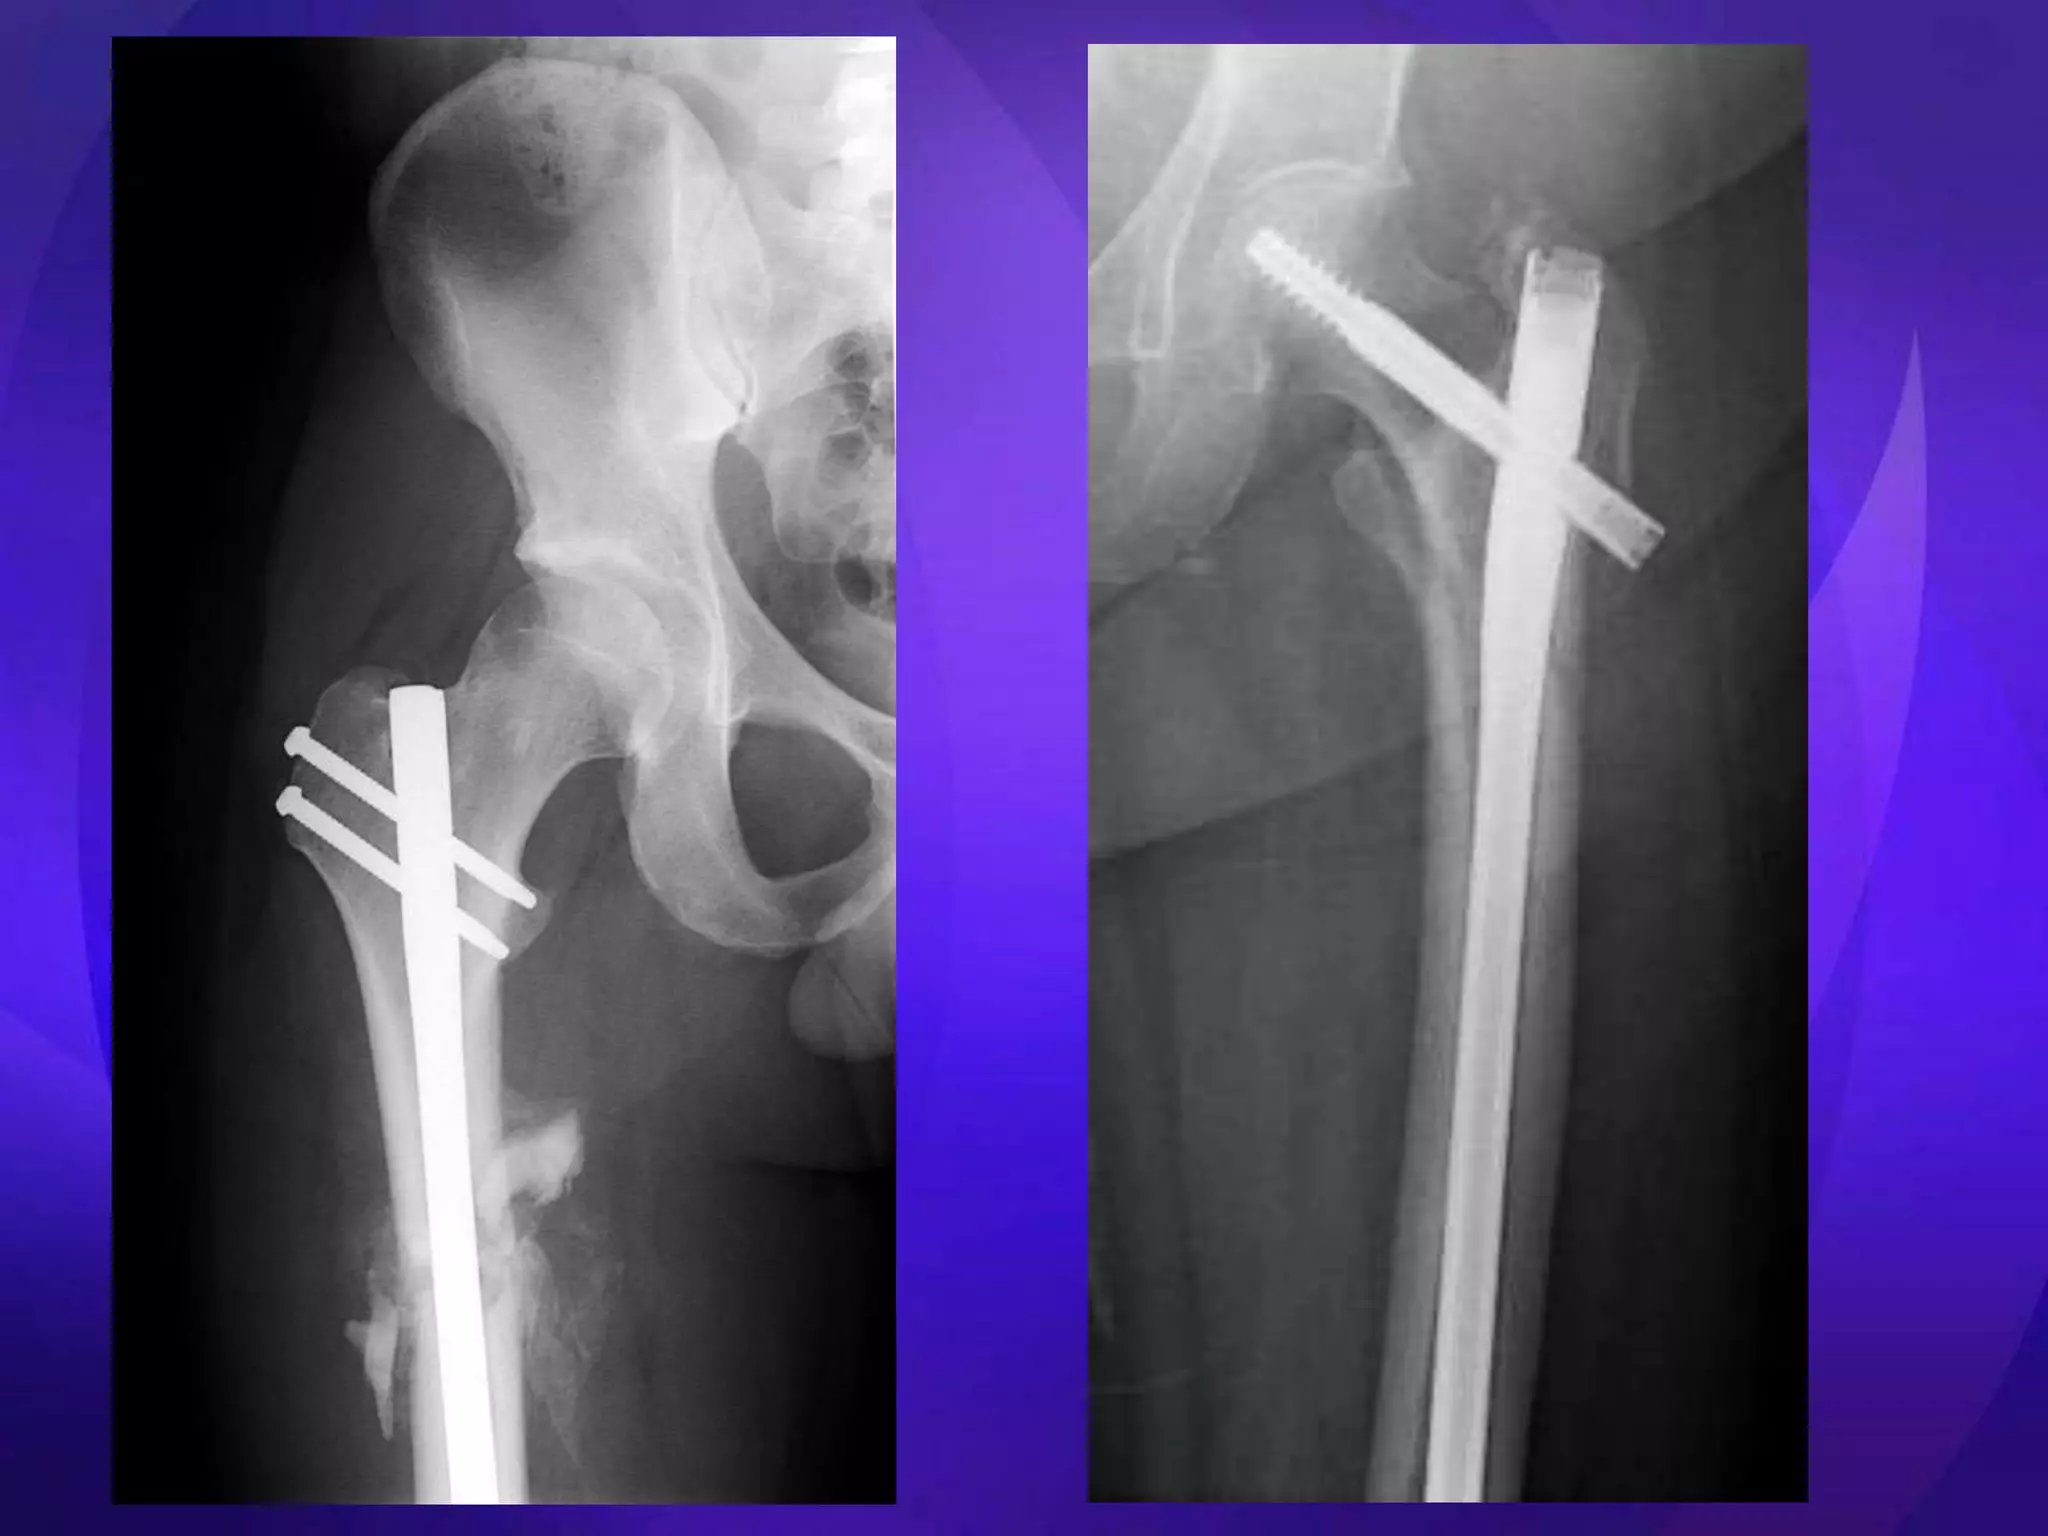

• Key issues – Medial cortical buttress – Reduction (esp varus deformity) • Extramedullary – ORIF – DHS, Medoff Sliding Plate, DCS, blade plate, locking plates • Intramedullary – Centromedullary – Cephalomedullary – Short vs long

Technically demanding • Soft tissue dissection • Plate/ screw breakage • 30% failure – Elderly – Unstable #s – Early weight bearing • Nonunions

• Easier toinsert than blade plate • Plate/ screw breakage • 20-30% failure – Elderly – Unstable #s – Early weight bearing • Nonunions

• Designed for intertrochanteric #s • Easier to insert • Entry point may be # • 25% failure – Loss of fixation • ? Should be avoided